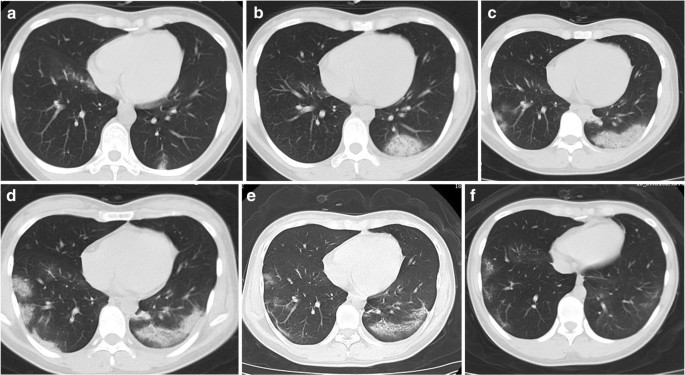

Fig. 3

A 26-year-old female patient presented with fever for 1 day. a The baseline CT scan (day 1, stage 1) obtained 3 days before the first positive RT-PCR test showed discrete GGO in her bilateral lower lobes. b The follow-up CT 2 days later (day 3, stage 1) showed that the size of GGO was markedly enlarged in the left lower lobe, accompanied by small-vessel thickening. c The follow-up CT obtained 3 days later (day 6, stage 2) showed that the lesions had progressed to consolidation in the left lower lobes and new GGO was identified in the right lower lobe. Crazy paving signs were detected in the left lower lobe. d Another 3 days later (day 9, stage 3), a CT scan showed lesion progression in the right lower lobe, accompanied by crazy paving signs. e The follow-up CT scan 3 days later (day 12, stage 3), 3 days before RT-PCR converting to negative, showed that the size of the lesions decreased, fibrotic lesions were predominant in the right lower lobe, and crazy paving signs dominated the left lower lesion. f Another 3 days later (day 15, stage 3), a CT scan demonstrated that the lesions were further improved and fibrotic lesions left